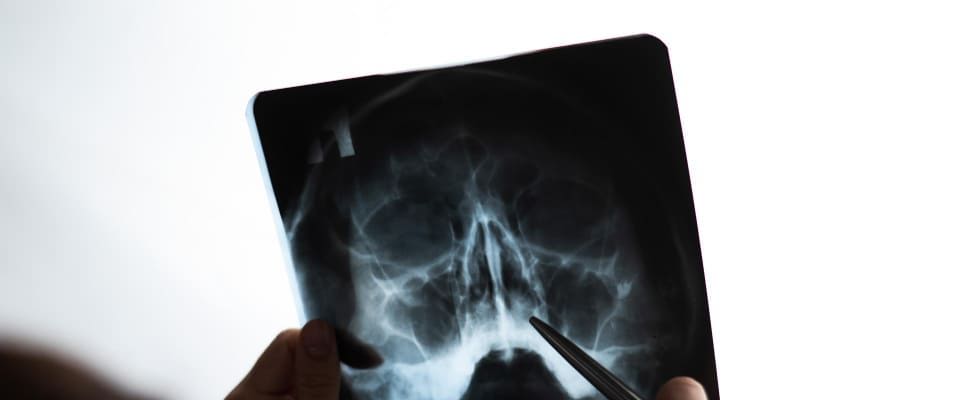

Rayos x senos paranasales

Los rayos X de los senos paranasales son una técnica de imagen utilizada para examinar los espacios huecos ubicados alrededor de la nariz y dentro de los huesos del cráneo. Este procedimiento es fundamental para diagnosticar diversas afecciones, como infecciones, inflamaciones, obstrucciones o tumores en los senos paranasales. Al proporcionar imágenes detalladas de estas estructuras, los rayos X permiten a los profesionales de la salud evaluar con precisión el estado de los senos paranasales y planificar el tratamiento adecuado para cada paciente.

Sirven para diagnosticar y evaluar diversas afecciones de los senos paranasales, como infecciones, inflamaciones, obstrucciones y anomalías estructurales. Este estudio permite a los médicos visualizar con claridad las cavidades de los senos paranasales y detectar problemas como sinusitis, pólipos nasales, fracturas óseas y tumores. Además, es una herramienta útil para planificar tratamientos quirúrgicos o monitorear la evolución de enfermedades crónicas en esta área.

Se utiliza una máquina de rayos X que emite una pequeña cantidad de radiación. El paciente se coloca en una posición específica y se le pide que permanezca inmóvil mientras se toma la imagen. La radiación atraviesa los tejidos y los huesos de la cara, creando una imagen detallada de los senos paranasales en una placa radiográfica. Esta imagen permite a los médicos identificar cualquier anomalía, inflamación o infección en los senos paranasales.